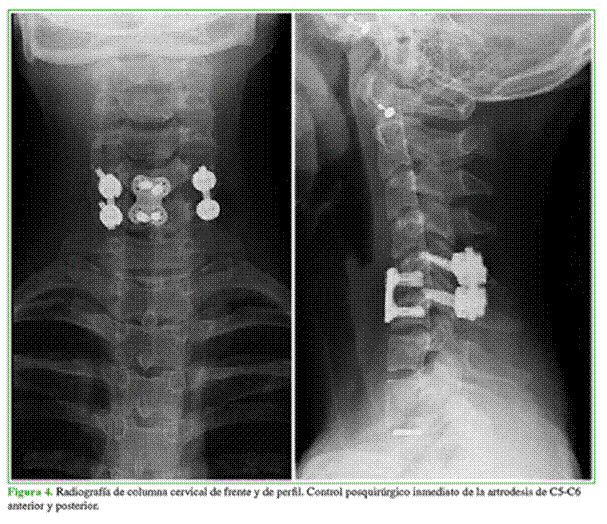

Se plantea la cirugía debido a la alta inestabilidad de la lesión. Se realiza artrodesis anterior y posterior de C5-C6 (Figura 4).